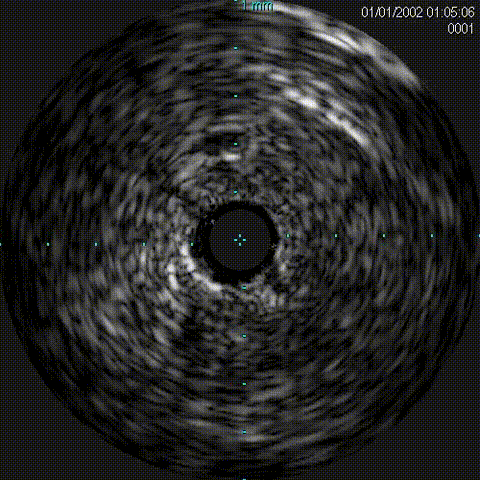

1、IVUS评估;

IVUS导管

Telescope™导引延长导管支撑,IVUS导管顺利通过

此病例为外膜钙化扭曲病变,超声导管无法通过,2.0mm小球囊通过困难,选用导引延长导管可以提高通过性,Telescope™导引延长导管在该病变中使球囊及IVUS导管通过顺利,器械输送效果及兼容性佳!

对于钙化病变,IVUS的选择还是必要的。如伴有钙化小结、环形钙化等,旋磨是一个好的选择,此病例无钙化小结及环形钙化,球囊扩张完全,所以未选择旋磨术。